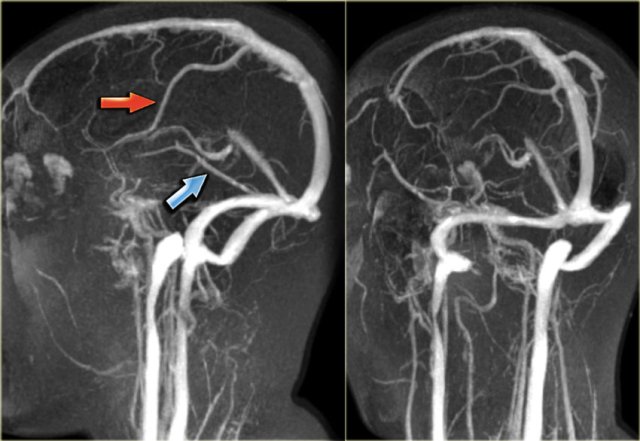

When you use MIP-projections, always look at the source images.

On the left a lateral and oblique MIP image from a normal contrast-enhanced MR venography.

Notice the prominent vein of Trolard (red arrow) and vein of Labbe (blue arrow).

On the left images of a patient with venous thrombosis, who was unconsious and did not respond to anticoagulant therapy.

There is thrombosis of the superior sagittal sinus (red arrow), straight sinus (blue arrow) and transverse and sigmoid sinus (yellow arrow).

Continue with the video of the thrombectomy.